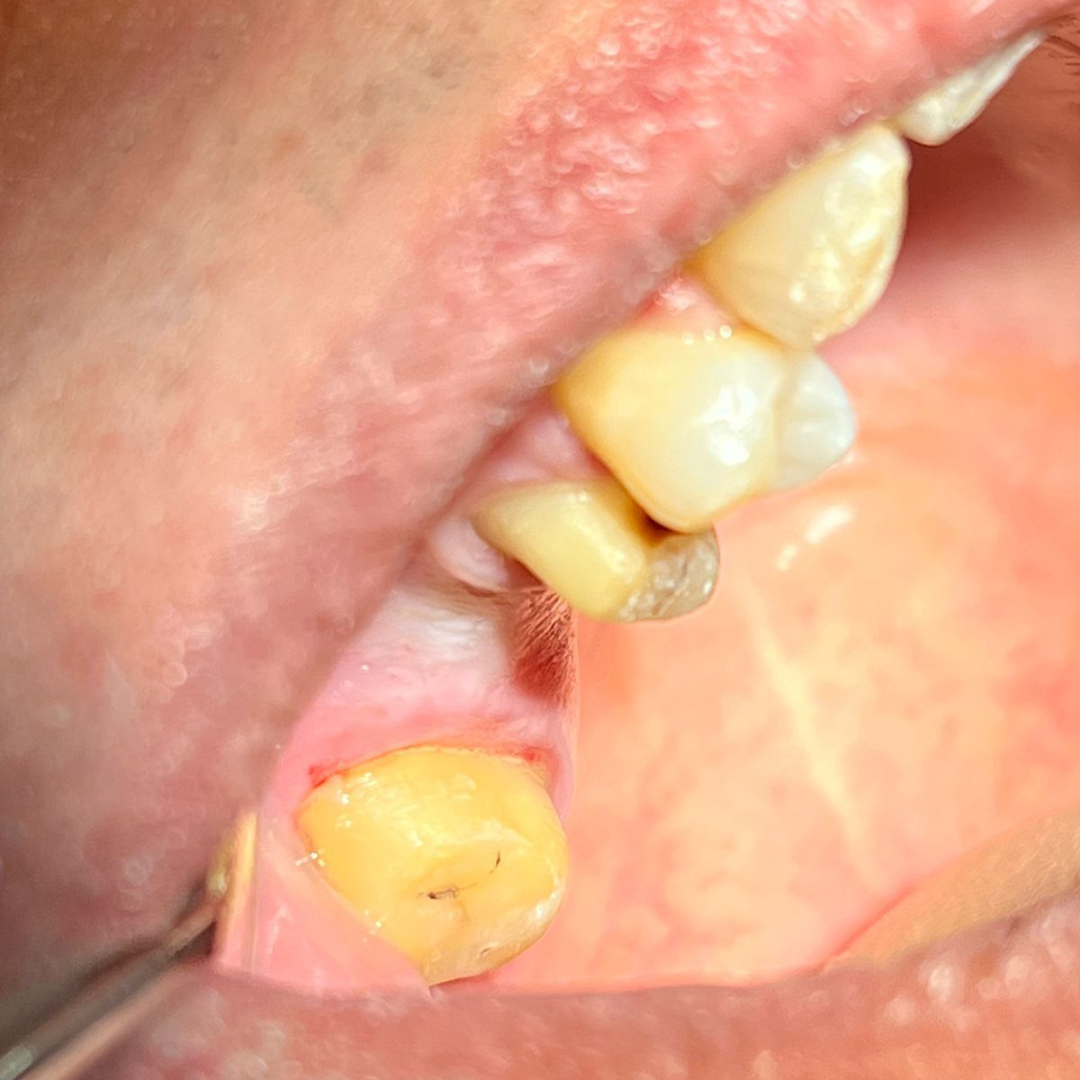

Throughout my studies, I immersed myself in learning, not just from books, but through hands-on experience at a local dental clinic. I spent countless hours there, treating patients and gaining invaluable practical skills. The joy and relief I saw in their eyes after each session were my greatest rewards. My humility and dedication earned me the love and respect of everyone around me.